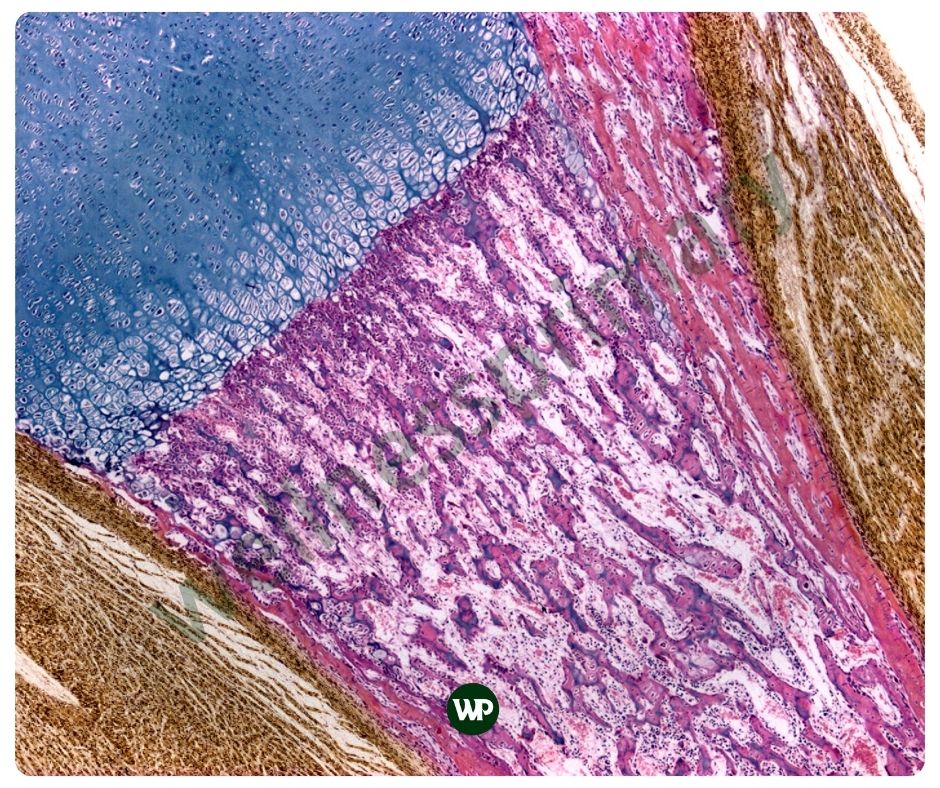

콘드로이친은 연골 조직에 존재하는 물질인데요. 주로 관절과 뼈의 건강에 중요한 역할을 합니다. 콘드로이친은 연골 내에 존재하는 중요한 글리코사미노글리칸의 일종으로, 주로 연골, 뼈, 힘줄, 인대 등에 많이 있습니다. 연골의 주요 구성 요소인 콘드로이친은, 관절의 부드러운 움직임을 도와주며 충격을 흡수해 통증을 완화해 줍니다. 또한 당과 단백질의 복합체인 프로테오글리칸의 일부로, 연골의 탄력성을 높이는데에도 도움이 됩니다. 주로 상어와 소의 연골에서 추출하여 영양제로 섭취할 수 있습니다.

인간의 연골의 두께는 무릎의 대퇴골 연골의 경우 약 3mm에서 4mm 정도로 가장 두껍습니다. 어깨 관절 연골은 약 1mm~2mm에 불과하지요. 연골은 우리의 움직임을 위해 매우 중요한 역할을 하지만 실제로 매우 얇습니다. 그래서 가능한 빨리 연골 보호에 신경을 써야 합니다. 콘드로이친 효능은 연골의 손상을 예방하며, 이는 특히 연령 증가에 따른 연골 퇴화를 막는 데 중요한 역할을 합니다. 콘드로이친은 이미 손상된 연골의 경우, 그 회복을 돕고, 연골 세포의 재생을 촉진하는 매우 중요한 역할을 합니다.